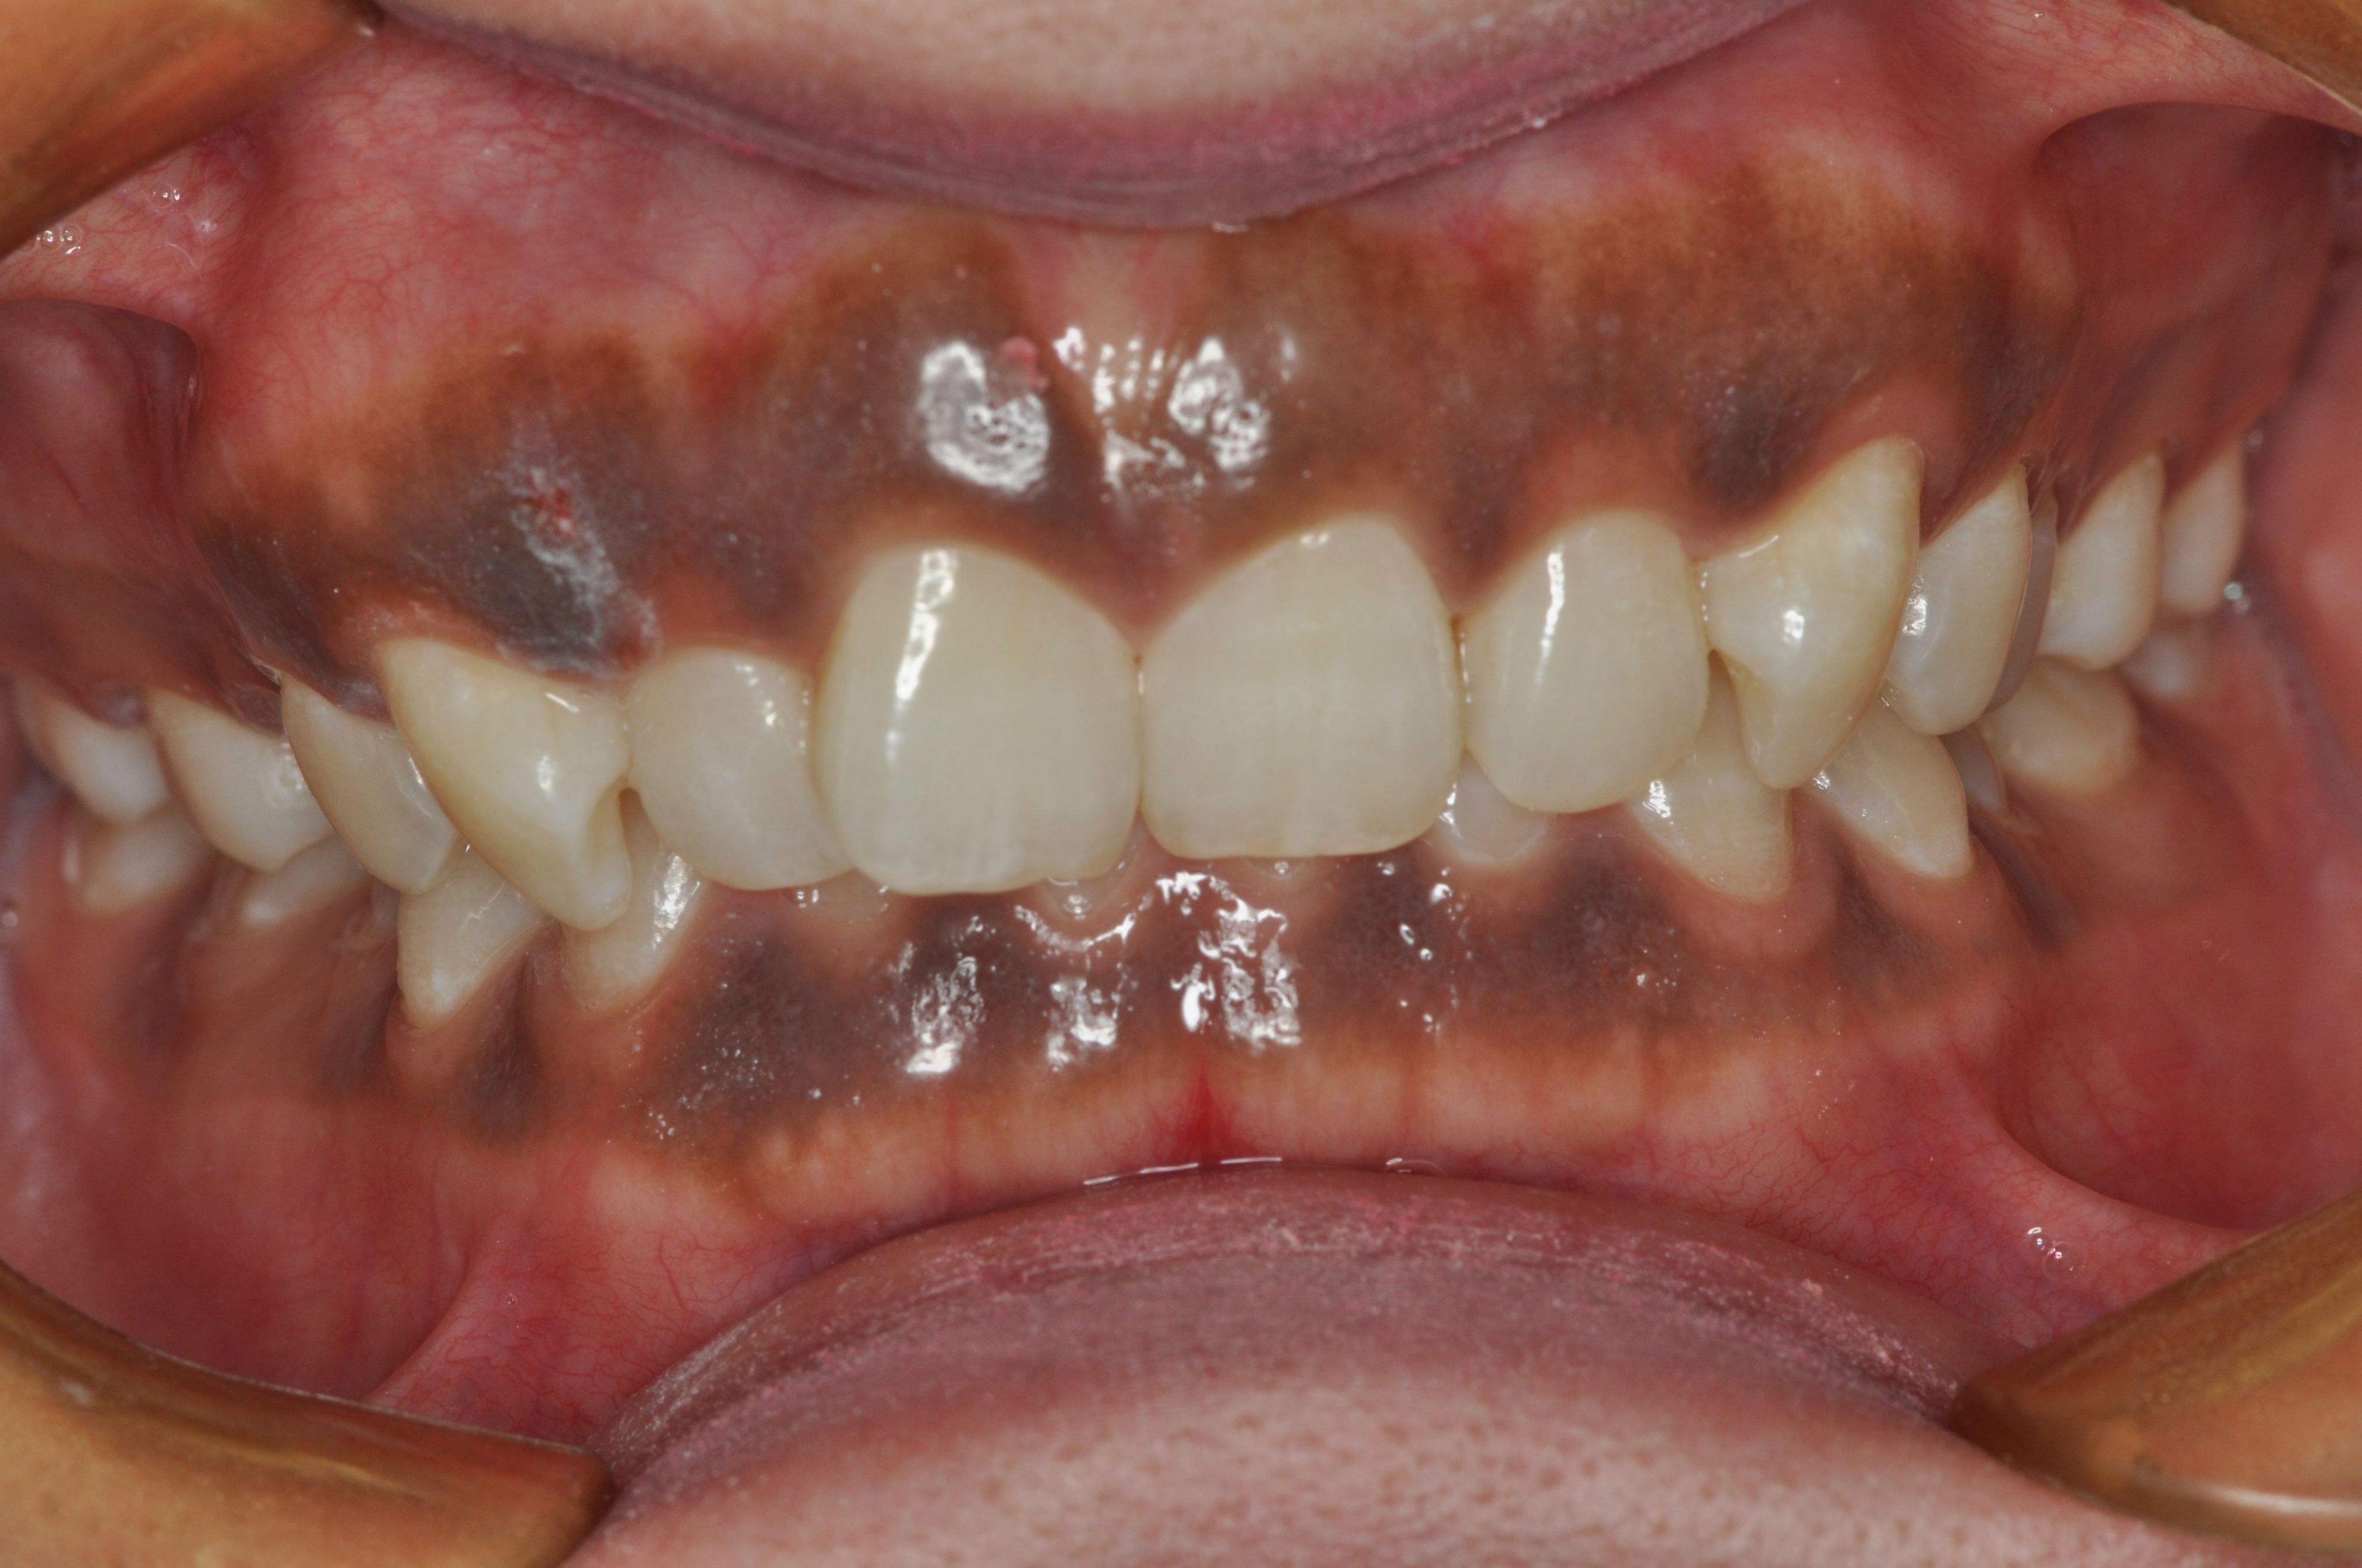

2、不良修复体造成的牙龈发黑

口内安装有金属烤瓷牙冠的人群,金属烤瓷冠与牙龈组织长期接触,局部金属离子析出沉积在牙龈,造成牙龈发黑的情况出现。

解决办法:及时拆除不良修复体,更换成全瓷牙冠。